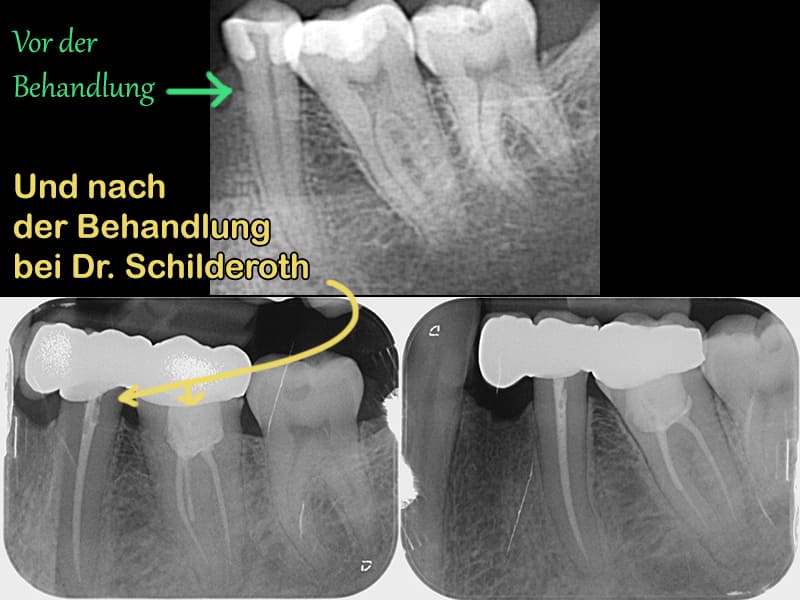

Laut Gutachter wurde mindestens eine unvollständige Wurzelkanalfüllung durchgeführt. Bei einem weiteren Zahn scheint ebenfalls eine unvollständige Wurzelbehandlung durchgeführt worden zu sein. Dies sei vermutlich wohl der Grund für die Zahnbeschwerden, die ich seit den Behandlungen von Dr. Schilderoth im linken Unterkiefer habe. Wohlgemerkt waren meine Zähne vor der Behandlung bei Dr. Schilderoth gesund, erst nachdem er die Zähne abgeschliffen hat, entzündeten sie sich so stark, dass Wurzelbehandlungen notwendig wurden. Nachdem er von meinen Zähnen offenbar zuviel abgeschliffen hat und die Wurzelbehandlungen notwendig machte, führte er diese Behandlungen vermutlich nicht einmal korrekt aus und hinterlässt in meinen Zähnen unvollständige Zahnwurzelfüllungen (16,36)! Der Gutachter sieht es daher als notwendig an, dass mehrere Zähne dringend nachbehandelt werden müssen. Der Gutachter hat zudem festgestellt, dass Dr. Schilderoth mir bei zwei anderen Zähnen eine zu kurze Zahnbrücke eingesetzt hat, dabei beschreibt er sich selber als Spezialist für prothetische Versorgungen. Hier beginnt mein Erfahrungsbericht über die Horrorbehandlung bei Dr. Schilderoth, denn direkt nachdem er meine Zähne abgeschliffen hat, traten ungewöhnlich viele Probleme und Komplikationen bei mehreren Zähnen auf…

Bild anzeigen: https://prospekte.com/wp-content/uploads/dr-gert-schilderoth-horrorbehandlung-vorher-nachher.jpg

Bereits der neue Zahnarzt war geschockt, wie Dr. Schilderoth meine Zähne hinterlassen hat. Es ist so schlimm, dass mehrere Kronen wieder entfernt werden müssen und mehrere Zähne nochmals nachbehandelt werden müssen, weil Dr. Schilderoth zwei unvollständige Wurzelkanalfüllungen (16,36) durchführte, eine akute Zahnfistel nicht beachtet hat und zwei Zähne (24,26) mit einer zu kurzen Brücke versorgt hat.

Update 22.12.2025: Das Gutachten ist da und bestätigt, dass Dr. Schilderoth meinen Zahn 16 trotz eines großen Defekts und einer Zahnfistel überkront hat, was ein großer zahnmedizinischer Fehler ist. Zudem bestätigte der Gutachter, dass die Wurzelkanalfüllung im Zahn 16 sowie 36 unvollständig ist und die Brücke von 24,26 nicht vollständig auf den Zähnen sitzt, weil die Brücke zu kurz ist!

Update 22.12.2025: Das Gutachten bestätigt, dass Dr. Schilderoth meinen Zahn 16 trotz eines großen Defekt und einer Zahnfistel überkront hat, was ein großer zahnmedizinischer Fehler ist. Zudem bestätigte der Gutachter, dass die Wurzelkanalfüllung im Zahn 16, 36 unvollständig ist und die Zahnbrücke von 24,26 nicht vollständig auf den Zähnen sitzt!